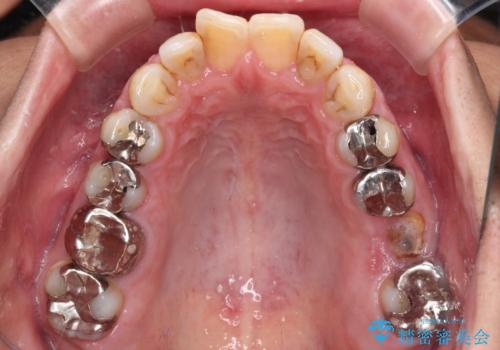

欠損と痛み 奥歯のむし歯治療

- 根っこの一部だけになった歯と咬むと痛みのある歯を気にして来院された患者様です。

上顎の歯根のみとなった歯は抜歯が必要であったので、抜歯を行い、インプラントあるいはブリッジのよる補綴治療を提案しました。

前後の歯は銀歯が装着されていたため、ブリッジによる補綴治療として、前後の歯もセラミックに置き換えることとしました。

下顎の根管治療がされた大臼歯は咬合時に痛みが認められたため、再度根管治療を行った後に補綴治療することとしました。